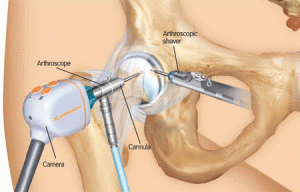

Артроскопия

Ревизия сустава и удаление поврежденных участков хрящевой ткани сустава, санация (удаление уплотнений, которые представляют собой остатки органических веществ), проводится промывание полости хряща во время лечения инфекционных заболеваний.